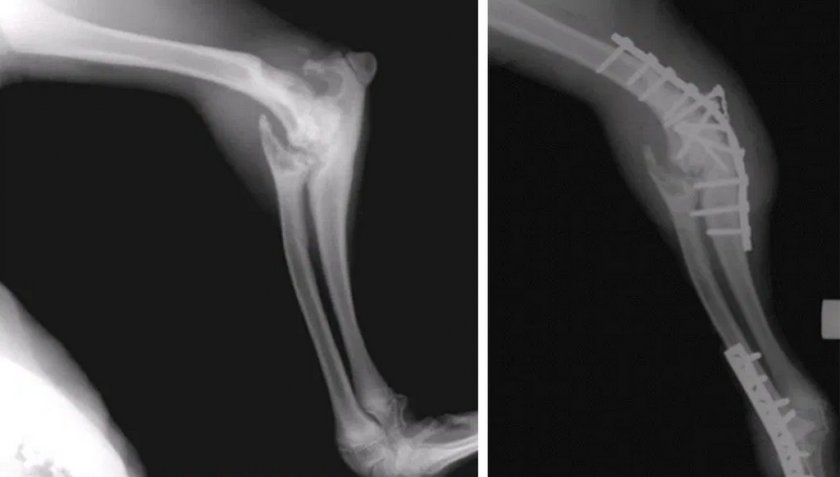

Аббревиатура «PAUL» расшифровывается как Proximal Abducting ULnar Osteotomy — проксимальное отведение ульнарного нерва (разновидность остеотомии). Этот метод используется для лечения медиального компартмент синдрома — одного из самых сложных заболеваний, охватываемых понятием дисплазии. В тяжёлой стадии болезнь вызывает у собаки не просто сильную хромоту, а полную невозможность пользоваться передней лапой, более того, именно этот вид дисплазии нередко поражает обе конечности, что делает животное абсолютным инвалидом. В процессе оперативного вмешательства хирург передвигает локтевую кость и прикрепляет её к специальной платине, после чего нагрузка при ходьбе переносится с внутренней (поражённой) на внешнюю (здоровую) часть скелета. Несмотря на то, что фактически сустав по-прежнему разрушен, двигательная функция у собаки может быть восстановлена на 80%.

Артродез — ещё один вид фиксации костей в суставе при помощи пластины. Хирург удаляет трущиеся между собой поверхности, располагая суставные элементы под правильным углом, без возможности свободного движения. После того, как перемещённые кости срастаются, на что обычно уходит примерно месяц, собака перестаёт ощущать боль при ходьбе, хотя и продолжает хромать. В результате артродеза сустава как такового у животного не остаётся, вместо него в месте локтя находятся «намертво» прикреплённые друг к другу кости.